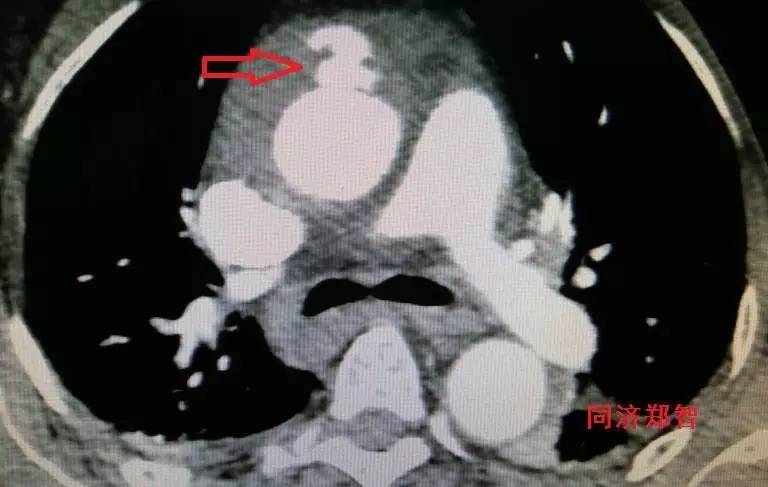

CT增强后证实为升主动脉壁间血肿(图4),如红箭头所示。

图4